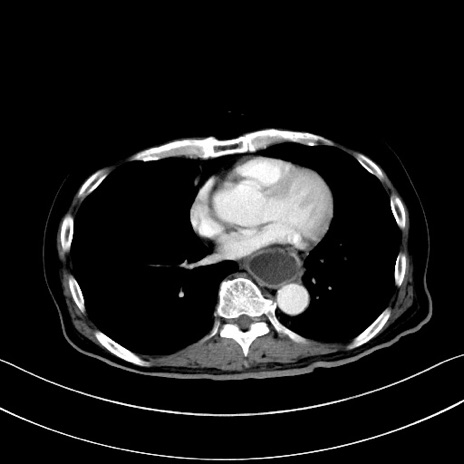

症例28(横断像)

【症例】60歳代男性

【主訴】嘔吐

【現病歴】胃癌にて胃全摘後。食思不振が悪化し、夜中に嘔吐することがある。

【既往歴】胃癌、胃全摘、脾摘、胆摘後

【データ】WBC 5900、CRP 10.56